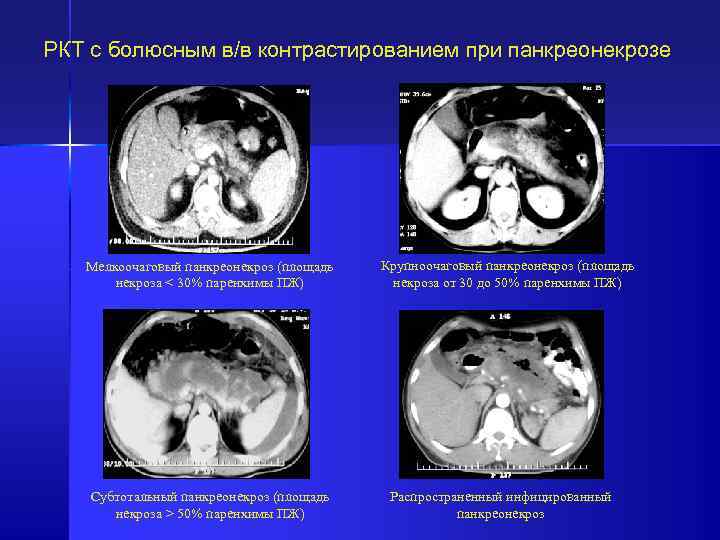

РКТ с болюсным в/в контрастированием при панкреонекрозе Мелкоочаговый панкреонекроз (площадь некроза < 30% паренхимы РКТ с болюсным в/в контрастированием при панкреонекрозе Мелкоочаговый панкреонекроз (площадь некроза < 30% паренхимы ПЖ) Субтотальный панкреонекроз (площадь некроза > 50% паренхимы ПЖ) Крупноочаговый панкреонекроз (площадь некроза от 30 до 50% паренхимы ПЖ) Распространенный инфицированный панкреонекроз